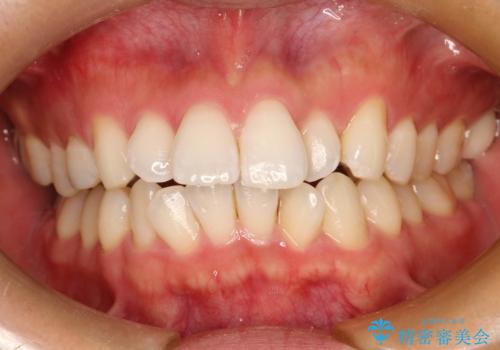

フルリンガル矯正 非抜歯でガタつきを整える

- フルリンガルワイヤーによる非抜歯治療を計画しました。